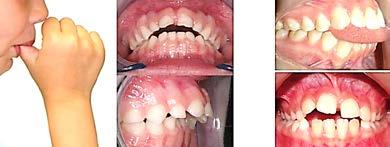

Por otro lado, los hábitos deletéreos como el hábito de dedo, hábito de lengua, el hábito de labio, síndrome de biberón y uso de distractores ora les, los cuales generan alteraciones en la dinámica de deglución, sella do labial, oclusión, respiración, una posición excéntrica mandibular y por consiguiente un desarrollo disarmo nico intermaxilar y de la orientación mandibular respecto a la base del crá neo (Figura 28).

La mordida abierta anterior es una maloclusión causada por la falta de contacto anterior, esta puede ser de origen dental o esquelético.1-3

La mordida abierta de tipo dental, es aquella en la que el patrón esquelético vertical no contribuye y generalmente se presenta de canino a canino, los incisivos maxilares se encuentran protruidos y proinclinados, generalmente se produce por un hábito, por el contrario la mordida abierta de tipo esquelética, es aquella donde el patrón esquelético sí influye, se caracteriza por una elongación del tercio inferior de la cara, rotación de la mandíbula en sentido de las manecillas del reloj, un patrón de crecimiento hiperdivergente y contactos sólo en molares.3-6

Su etiología es multifactorial rela cionada con la herencia y el medio ambiente. Los factores etiológicos ambientales se observan común mente durante el desarrollo infantil y generalmente se asocian con hiper trofia amigdalar, respiración bucal y hábitos bucales nocivos que incluyen chuparse el pulgar, el chupón y la deglución atípica,5-8 esta se caracte riza por la interposición de la lengua colocándose entre las arcadas den tarias cuando se realiza la acción de deglutir, lo que se podría denominar como lengua protráctil.8